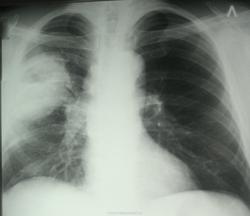

Контроль от 18.12.13

Контроль от 27.12.13

Представлена динамика за 21 день. Наверное, для констатации динамики абсцесса придется подождать еще пару месяцев.

По представленному случаю: в пользу обычного абсцесса объёмное увеличение верхней доли с провисанием междолевой плевры. В таких случаях пишу динамика "-", конс.торакального хирурга.

Еще один сильный аргумент в пользу рака - толстая стенка вокруг полости

На всех снимках хорошо виден дренирующий бронх, если бы был абсцесс с жидким содержимым, то давно бы уже продренировался до тонкой стеночки..